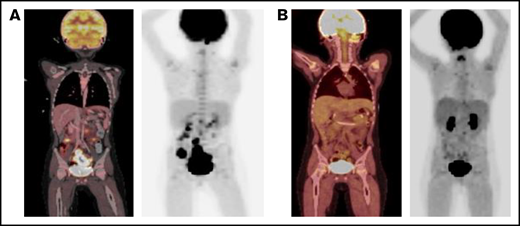

PET scan response before and after blinatumomab treatment. (A) PET scan on day +92 showing concern for PTLD with multifocal, fluorodeoxyglucose-avid uptake and lymphadenopathy in the abdomen and pelvis. (B) PET scan on day +179 showing significant metabolic and structural improvement of abdominal and pelvic lesions 1 day after completion of blinatumomab. PET, positron emission technology; PTLD, posttransplant lymphoproliferative disease.

Given this disease progression and the desire to avoid cytotoxic chemotherapy in a patient with FA, we administered EBV active, HLA-A24–restricted match (Michael D. Keller, Jeffrey Modell Diagnostic and Research Center for Primary Immunodeficiency Disorders at Children's National Health System, e-mail, 3 January 2021 and 2 January 2022 ), third-party, EBV-specific, cytotoxic T lymphocytes (CTLs) on day +116 (clinicaltrials.gov NCT03475212). EBV titers continued to increase 4 weeks after CTL infusion, with a peak at 90 872 IU/mL. A PET scan again showed disease progression, including new and worsening liver lesions and concern for bowel and sacral involvement with no central nervous system lesions. A biopsy of a liver lesion demonstrated ongoing PTLD, with similar immunohistochemical staining, as well as diffuse CD19+ staining. The cerebrospinal fluid and bone marrow aspiration were negative for disease. Given the improving immune reconstitution with a total CD3 count of 1342 cells per microliter, blinatumomab (15 μg/m2 per day) was administered on day +150 as a 28-day continuous IV infusion and was well tolerated. One day after completion of the infusion, a PET scan demonstrated significant metabolic and structural improvement of the liver, bowel, and sacral lesions with resolution of the abdominopelvic adenopathy (Figure 1B). EBV viremia decreased from 74 186 IU/mL at the time of blinatumomab initiation to undetectable over 39 days. At the time of this report, the patient is >1 year after HCT and 7 months after completion of blinatumomab and is clinically well without detectable EBV viremia, other viral reactivation, or clinical signs of GVHD. His clinical course is summarized in Figure 2.